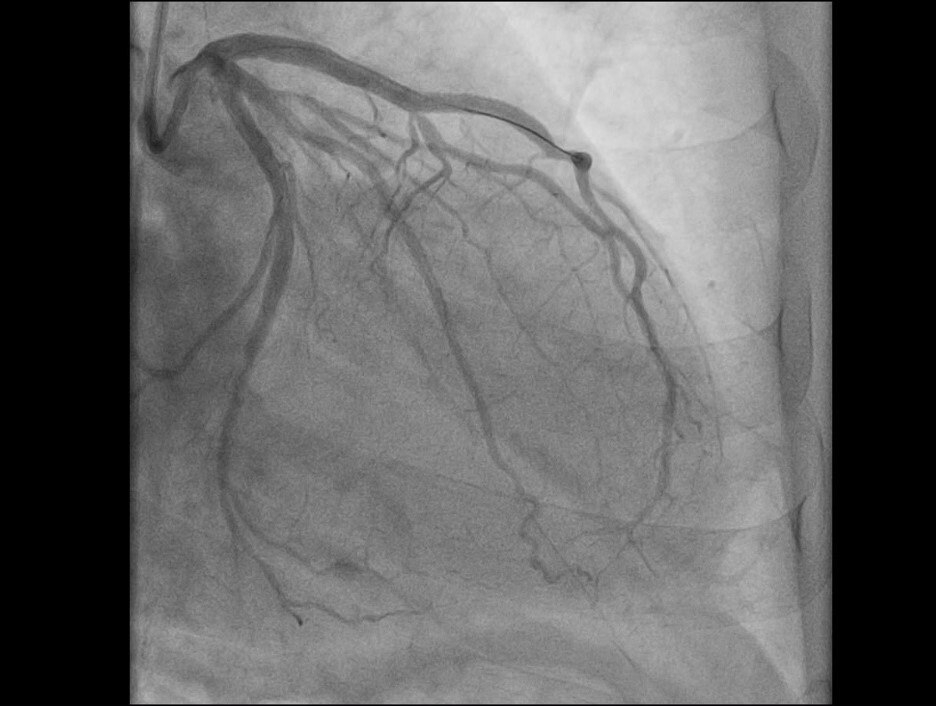

«Пациент, мужчина 59 лет, поступил после того, как почувствовал острую боль в груди во время уборки снега. Бригада „скорой“ диагностировала острый инфаркт миокарда. В ходе обследования была выявлена острая тромботическая окклюзия передней межжелудочковой артерии — сосуда, который неофициально называют „артерией вдов“ из-за высокой летальности при его поражении», — рассказали в балаковской больнице.

Операционная бригада выполнила экстренное стентирование артерии, в результате чего её проходимость была полностью восстановлена. После этого пациента выписали для продолжения реабилитации на амбулаторном этапе.